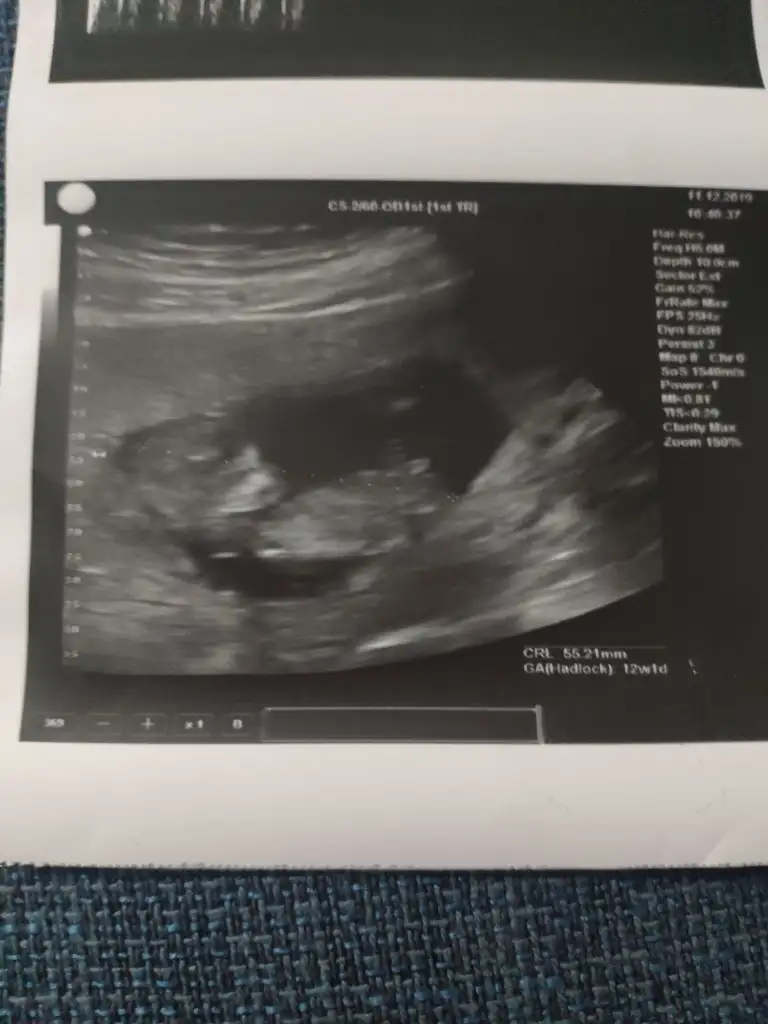

Bu da venim 12 haftalık ultrasonum.Doktor bir dahaki sefere anlaşılır dedi ama tahmin edebilirseniz çok sevinirim.